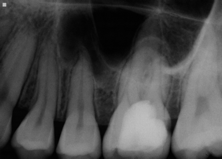

Conventional endodontic treatment with alloy core build up

Conventional Endodontic Treatment with Post and Core Coronal Restoration